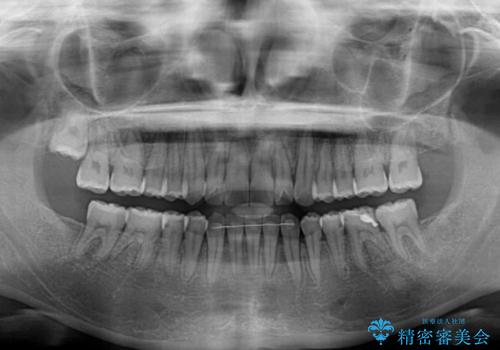

- 上下前歯の隙間を気にして来院された患者様です。

下顎前歯が1本欠損しており、上下小臼歯はクロスバイトとなり、上下前歯の接触もないという不正咬合の状態でした。

クロスバイトはワイヤー矯正が得意とするところであり、上下前歯の非接触や開咬はインビザラインの得意とするところであるので、ワイヤー装置により事前にクロスバイトを改善し、その後にインビザラインにて仕上げていくこととしました。